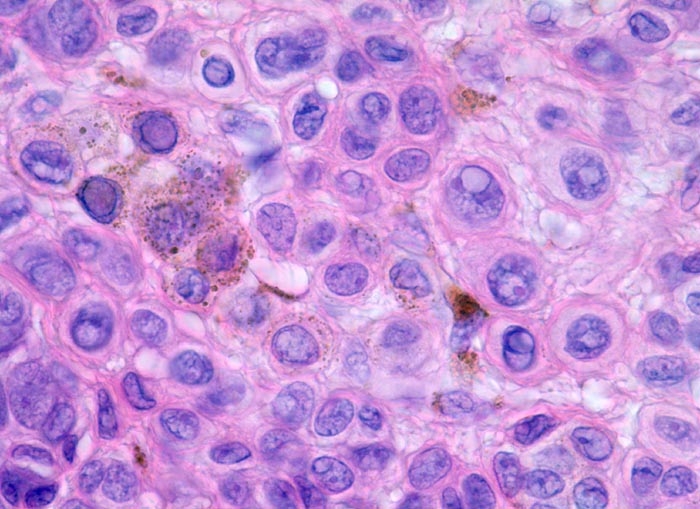

• Oberflächliche Tumorzellen enthalten teilweise körniges braunes Melaninpigment.

• Angrenzend an die pigmentierten Zellnester sind Melanophagen erkennbar, deren Zytplasma mit Melaningranula angefüllt sind.

• Die oberflächlichen Naevuszellen zeigen reichlich helles, teils pigmentiertes Zytoplasma und helle ovale Kerne mit kleinen, deutlich erkennbaren Nukleolen. Zur Tiefe hin werden die Naevuszellen kleiner, haben weniger Zytoplasma und dunkle kleine Kerne ohne gut erkennbaren Nucleolus. Die Zellnester werden zur Tiefe hin ebenfalls kleiner (=Ausreifung).

• Keine Mitosen, keine Zellatypien.

Kennzeichnend für einen gutartigen Naevuszellnaevus ist dessen Symmetrie und die Ausreifung der intradermalen Naevuszellen von oberflächlich gelegenen grossen, runden, pigmentierten Zellen in grossen Nestern, zu tiefer gelegenen kleineren, runden, nicht pigmentierten, in kleineren Nestern oder einzeln liegenden Zellen und in älteren Läsionen zu spindeligen Zellen mit neuralem Phänotyp mit Verlust der melanozytären Differenzierung (sogenannter Neuronaevus). Gewöhnliche Naevi zeigen keine zytologischen Atypien und die dermale mitotische Aktivität ist minimal. Es existieren verschiedene Varianten erworbener Naevi, welche klinisch und/oder histologisch Melanome imitieren können. Zu diesen Varianten gehören Halo Naevi, kombinierte Naevi, Spitz Naevi, blaue Naevi und dysplastische Naevi.